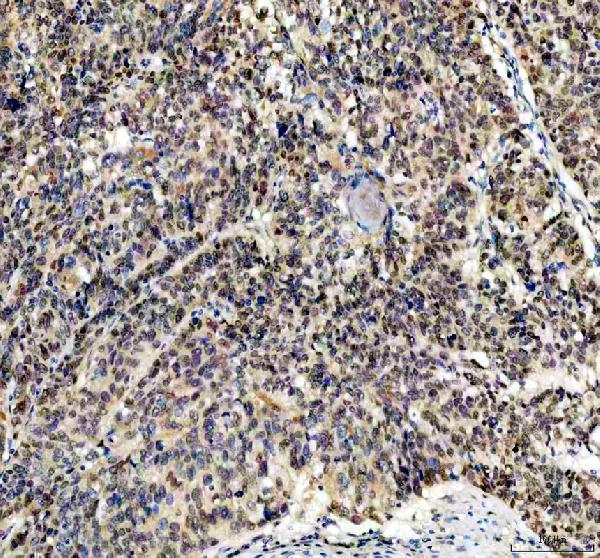

Expressed in granulosa and cumulus cells. Expressed in hepatocellular carcinoma cells, but not in non- cancerous liver tissue.